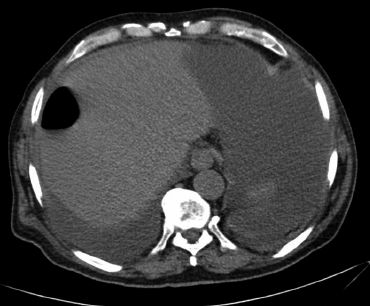

Introducción: La ascitis quilosa es la presencia de líquido linfático en la cavidad peritoneal. Como consecuencia de una cirugía abdominal es muy infrecuente, encontrando 5 casos previos en la literatura revisada tras colecistectomía. Se presenta el caso de un paciente con dicha complicación,su manejo y una revisión de la literatura.

Materiales y Métodos: Varón de 77 años, quiloperitoneo 21 días después de realización de colecistectomía programada por colecistitis aguda.

Resultados: Se realiza drenaje percutáneo con débito de 5 L en 24 horas, se inicia octreótido subcutáneo y nutrición parenteral total. Al tercer día disminuye el débito por el drenaje, por lo que se inicia dieta rica en triglicéridos de cadena media con buena evolución posterior. De los 5 casos previos tras colecistectomía, el 60% se resolvió con tratamiento conservador, un paciente precisó reintervención y otro colocación de un shunt portosistémico intrahepático trasnyugular (TIPSS).